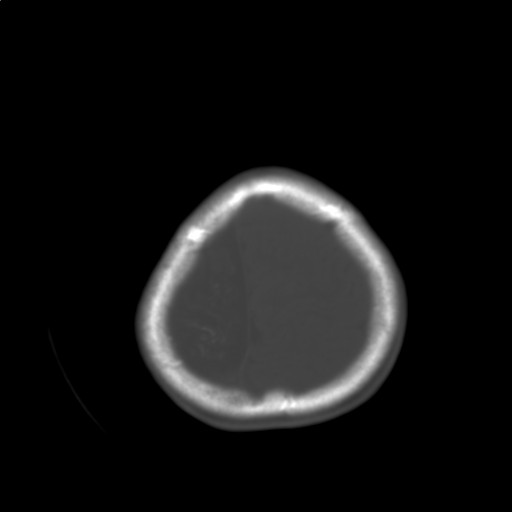

标题: PED3416:F,12Y,智力下降,学习成绩差,8个月时发过高烧。

右侧半球萎缩,软化,多量脑回样钙化,考虑颅面血管瘤病,建议dsa检查

右侧半球萎缩,软化,多量脑回样钙化,同侧颅盖板障增宽,考虑颅面血管瘤病,建议dsa检查与化脓性脑膜炎后遗改变鉴别。